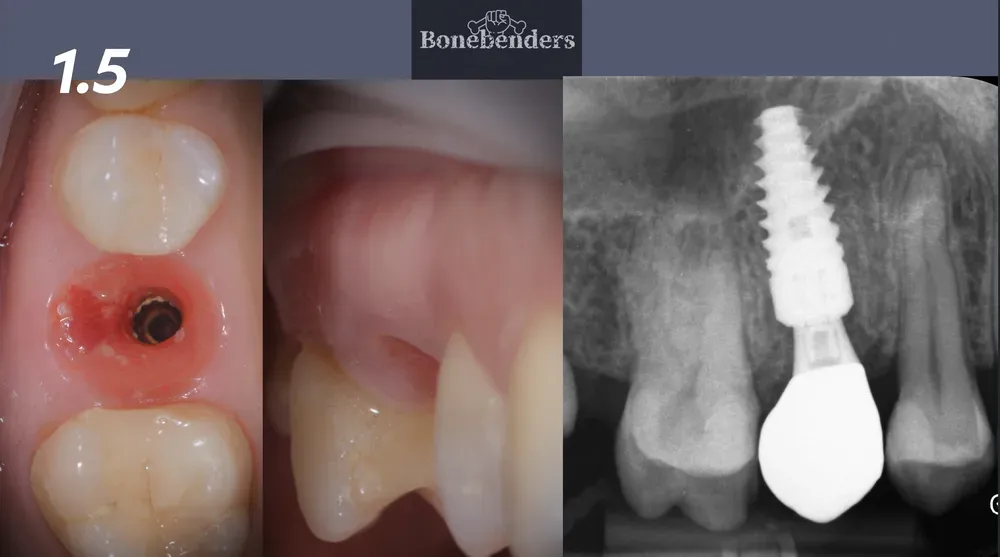

La foto finale del caso clinico di carico immediato rappresentato in sequenza nei paragrafi precedenti dimostra l’efficacia della tecnica di espansione apicale con il kit Bonebenders.

Questo caso, come tutti i miei casi di carico immediato singolo, sfrutta i principi del “Chamber Concept” di Marco Degidi.

Risultato finale impianto a carico immediato con conservazione profili emergenza tramite chamber concept

Immagine finale del caso di impianto a carico immediato rappresentato nell’articolo, con la conservazione totale dei profili di emergenza grazie alla tecnica con innesto eterologo e chamber concept di Degidi.